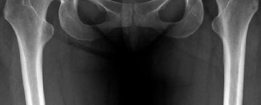

Radiographic assessment must be exhaustive. A standardized anteroposterior (AP) radiograph of the pelvis, centered over the symphysis pubis with neutral pelvic tilt and rotation, is mandatory. On this view, the LCEA, Tönnis roof inclination angle, and extrusion index are calculated. For instance, an LCEA of 18° and a roof inclination of 20° confirm severe lateral and superior uncoverage. A false profile view of the Lequesne and de Sèze is critical for assessing anterior coverage (anterior center-edge angle) and anterior joint space. Dunn 45° and 90° views, or a cross-table lateral, are utilized to evaluate the femoral head-neck junction for CAM morphology.

From an osseous perspective, the normal adult hip relies on a delicate balance of version and coverage. The acetabulum is typically anteverted approximately 15° to 20°, with a normal LCEA between 25° and 39°, and a roof inclination angle approaching zero. The proximal femur normally exhibits 10° to 15° of anteversion. In our complex instability cohort, this relationship is severely distorted. A patient may present with an LCEA of 18° (frank dysplasia) and a roof inclination of 20° (a steep, up-sloping sourcil), leading to a severely diminished weight-bearing surface area. When this is compounded by high femoral anteversion—such as 36° measured on MRI—the femoral head is driven anteriorly. This creates a functional anterior uncoverage that is exponentially worse than the radiographic coronal measurements imply.